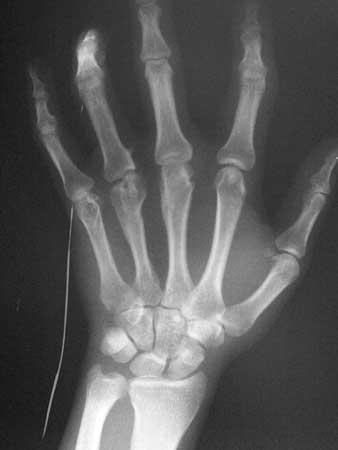

男性患者,31岁,中指和无名指活动障碍,无名指近节指间关节屈曲。

骨性关节病,建议了解病史

我认为有可能病人长期从事高创伤工作所以的创伤性关节炎。

1、三、四掌骨远端陈旧性骨折;2、三、四掌指骨关节创伤性关节炎。